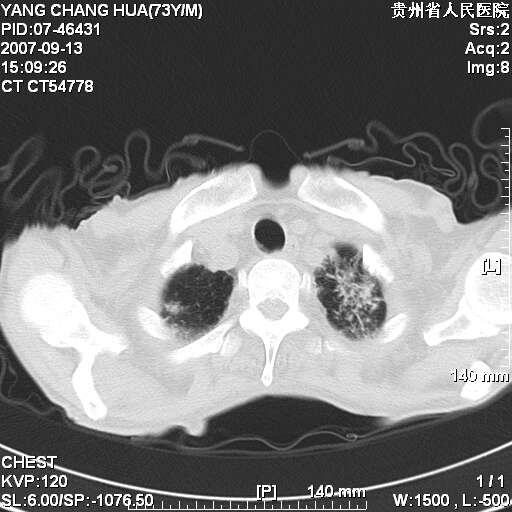

双肺点片状影,以双上肺改变明显.双侧胸腔积液.为感染性病灶,但不除外结核.

双上肺继发型肺结核。

双肺散在斑片状及多发小结节状阴影,边缘模糊,双上肺野明显,双侧胸膜腔少量积液,纵隔及肺门区未见明显肿大淋巴结,肝脾肿大,脾内见多发低密度区,结合临床考虑恶性淋巴瘤(肺内表现为肺炎肺泡型),单看影像表现,肺结核不能排除。建议结合实验室检查或表浅淋巴结活检。